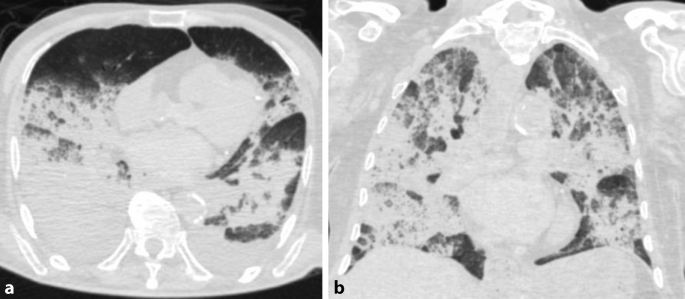

Having pneumonia from a. In diagnosis chest computed tomography CT manifestations can supplement parts of limitations of real-time reverse transcription polymerase chain reaction RT-PCR assay. Persistent Viral Presence Determines the Clinical Course of the Disease in COVID-19.

This is due to abundant ACE2 receptor expression in the lung parenchyma specifically on the acinar side of lung epithelial cells pneumocytes within the alveolar spaces allowing virus entry Fig 1 5. Dhypoxmie certains patients Covid-19 prsentent une gne respiratoire plus ou moins. 20200627 To compare the chest computed tomography CT findings of coronavirus disease 2019 COVID-19 to other non-COVID viral pneumonia.